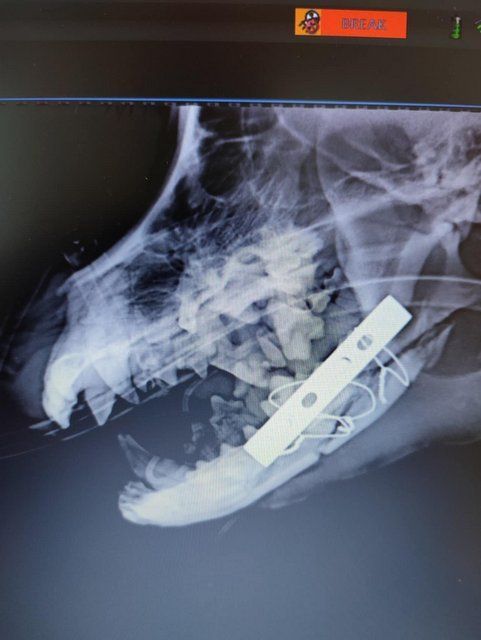

Röntgenbilder zeigten das Ausmaß der Zerstörung des Unterkiefers und den Bruch eines Beines.

Dieser Hund muss grausame Schmerzen haben, Zähne sind aus der Verankerung gerissen und sein Gesichtsschädel ist nicht mehr symmetrisch. Ein großes Stück des Unterkiefers ist komplett abgebrochen.

Camush Kopf ist wieder symmetrisch, der Kiefer wird jetzt mit Platte und Verdrahtung zusammengehalten und ein paar Zähne fehlen jetzt.

Sein Beinbruch ist ein offener Unterarmbruch von Elle und Speiche, der noch nach Erstversorgung operiert werden muss.